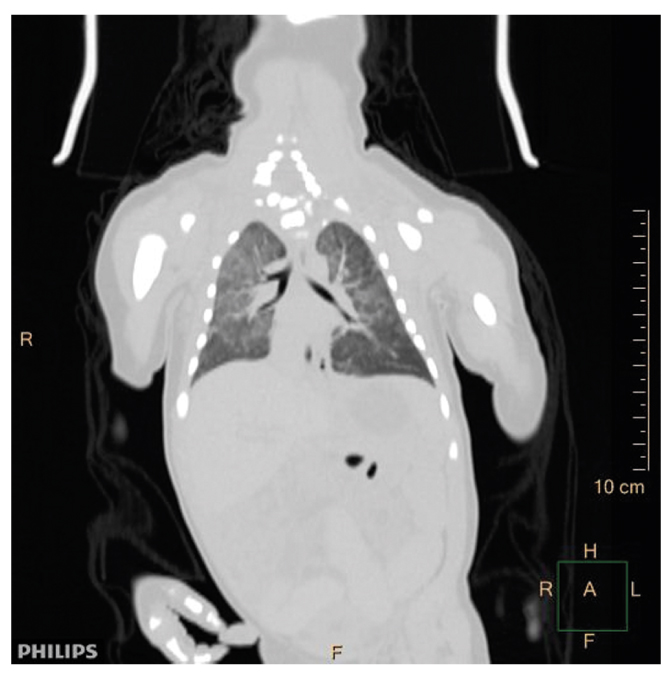

При исследовании трупа с помощью метода КТ врачом-рентгенологом выявлены диффузные изменения плотности вещества мозга — вероятно, сочетание гипоксических и посмертных изменений. Данных за интракраниальную гематому не получено. Дополнительная полость 5-го желудочка — вариантная анатомия (рис. 2). Содержимое в носоглотке. Небольшое количество содержимого в полости рото- и гортаноглотки с сохранением их просветов. Признаки кардиомегалии. Признаки гинекомастии. Диффузная гиперплазия обоих надпочечников. Вывих левой плечевой кости (рис. 3). Расправление легких. Наличие воздуха в петле тощей кишки и нижнеампулярном отделе прямой кишки (рис. 4). Жидкостное содержимое в желудочно-кишечном тракте с равномерным распределением (рис. 5). Наличие ядер окостенения в грудине (рис. 6). Наружный нос и ушные раковины сформированы правильно.

Рис. 4. КТ, фронтальная реконструкция, легочное окно: легкие расправлены, широко прилежат к грудной стенке; газ в петле тощей кишки.

Fig. 4. Computed tomography scan, frontal reconstruction, pulmonary window: the lungs are straightened, widely adjacent to the chest wall; gas in the jejunal loop.

На основании полученных данных сделан вывод: новорожденный является зрелым, доношенным и жизнеспособным, продолжительностью внутриутробной жизни около 10 лунных месяцев. Ребенок родился живым, о чем свидетельствуют положительные плавательные гидростатические легочная и желудочно-тонкокишечная пробы, данные предсекционного КТ и судебно-гистологического исследований.